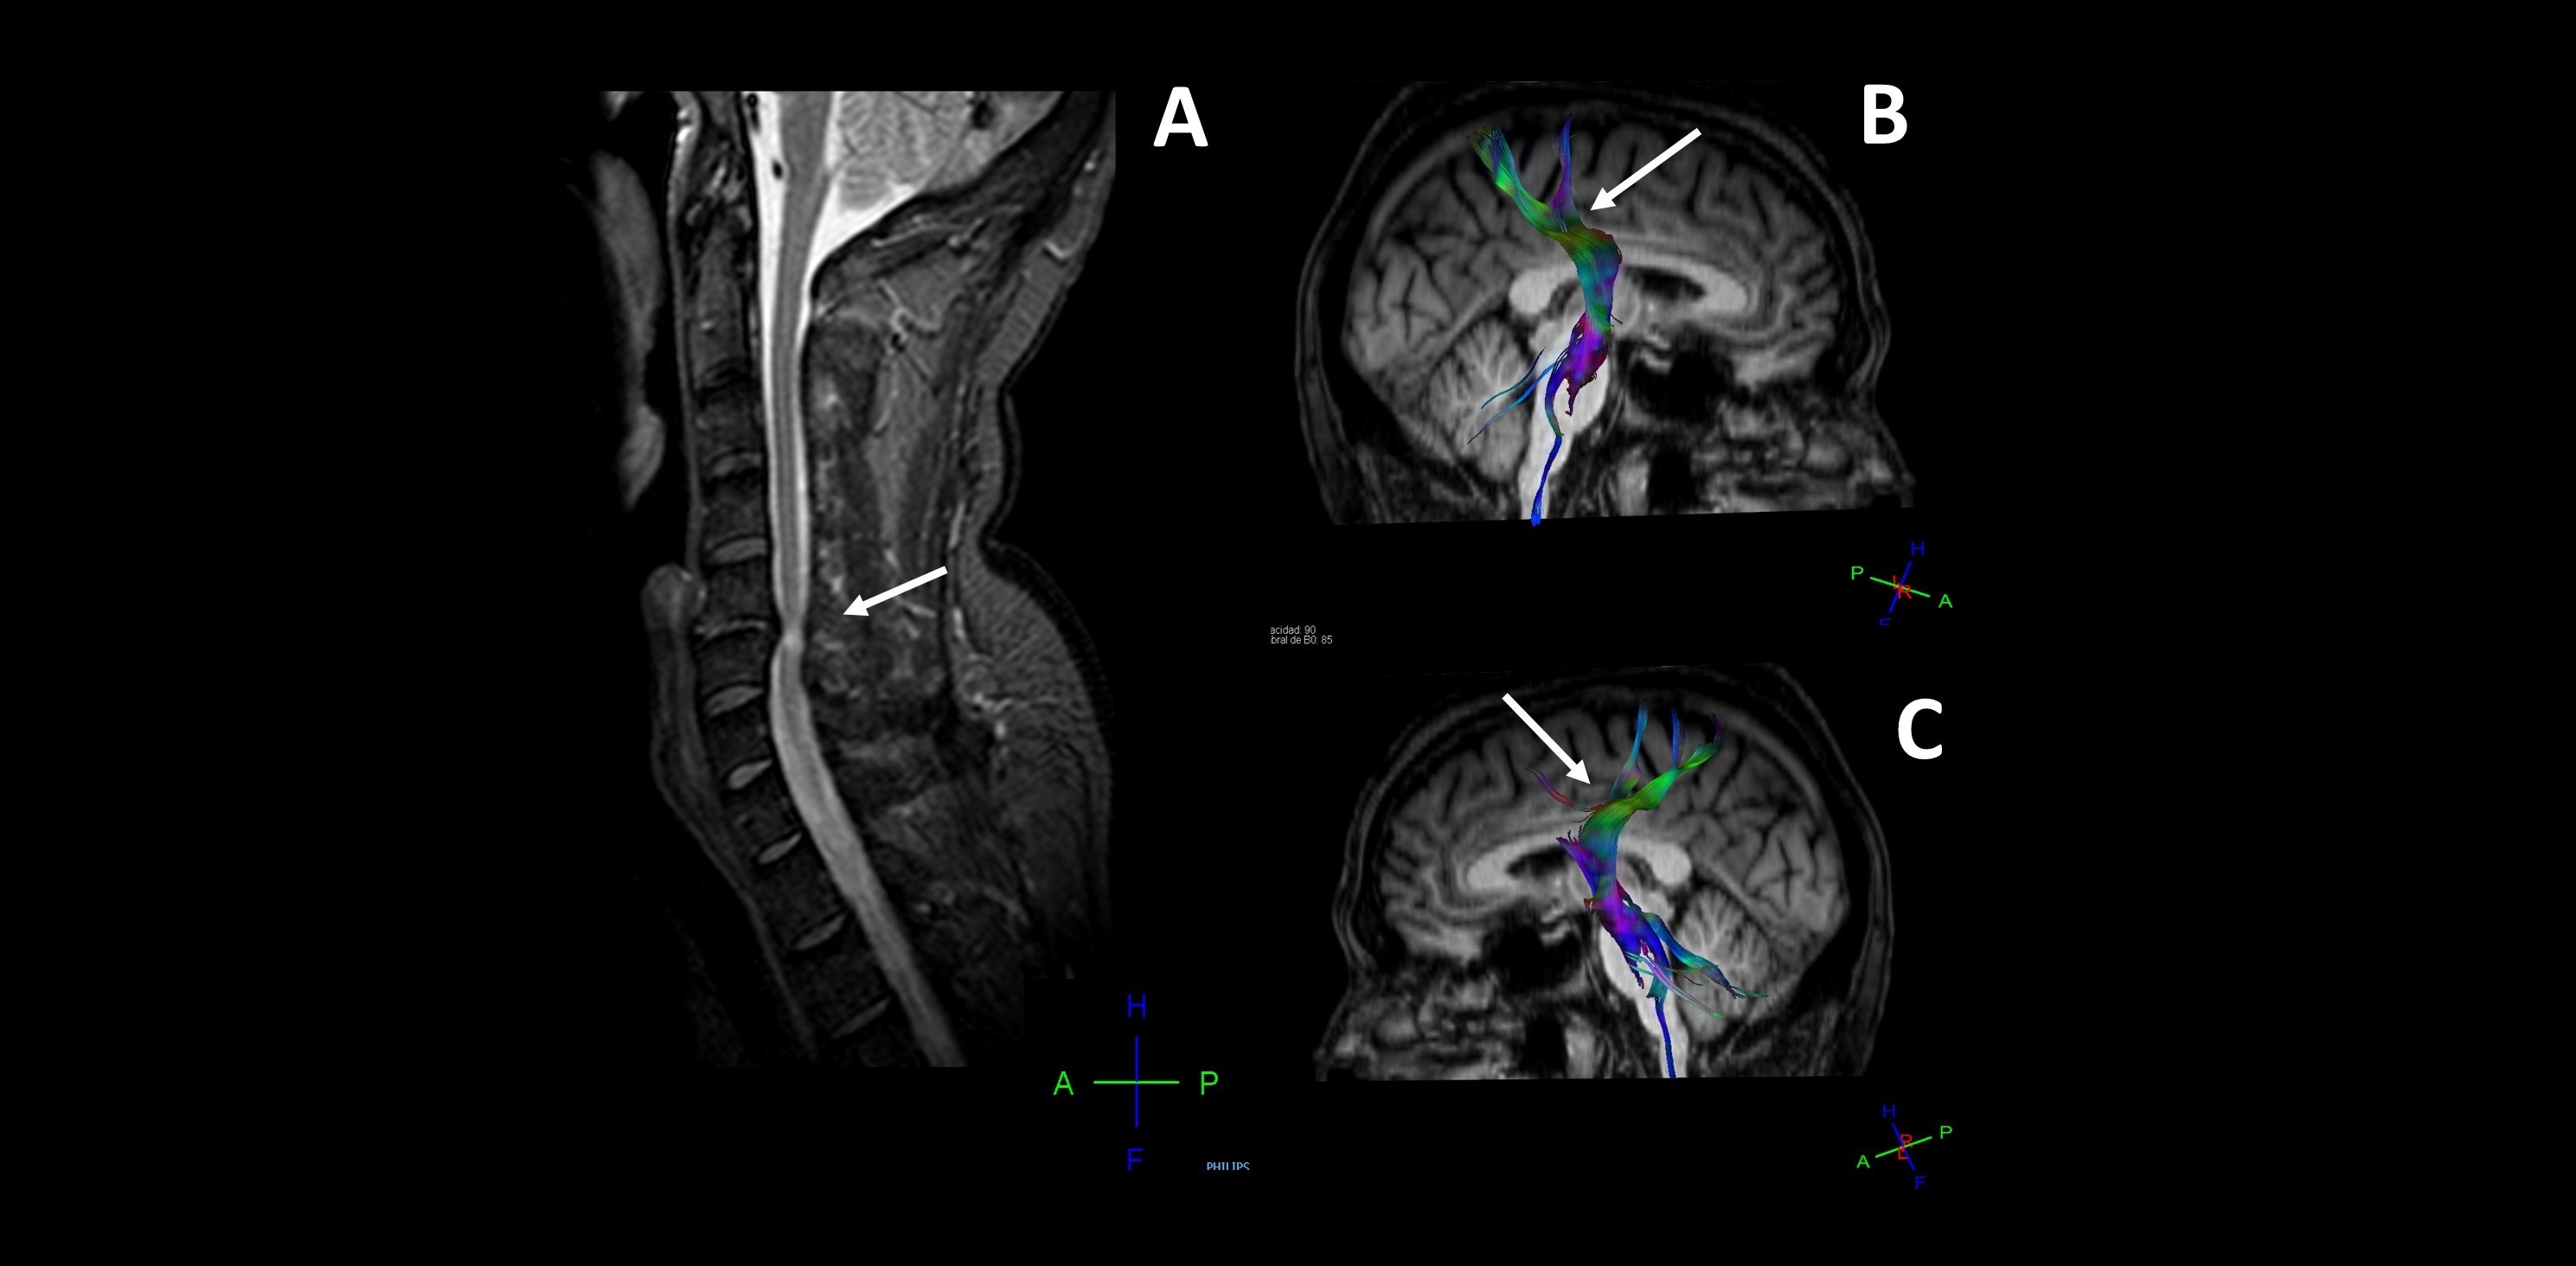

Detectan daño cerebral en pacientes con hernias cervicales mediante técnicas de neuroimagen e inteligencia artificial